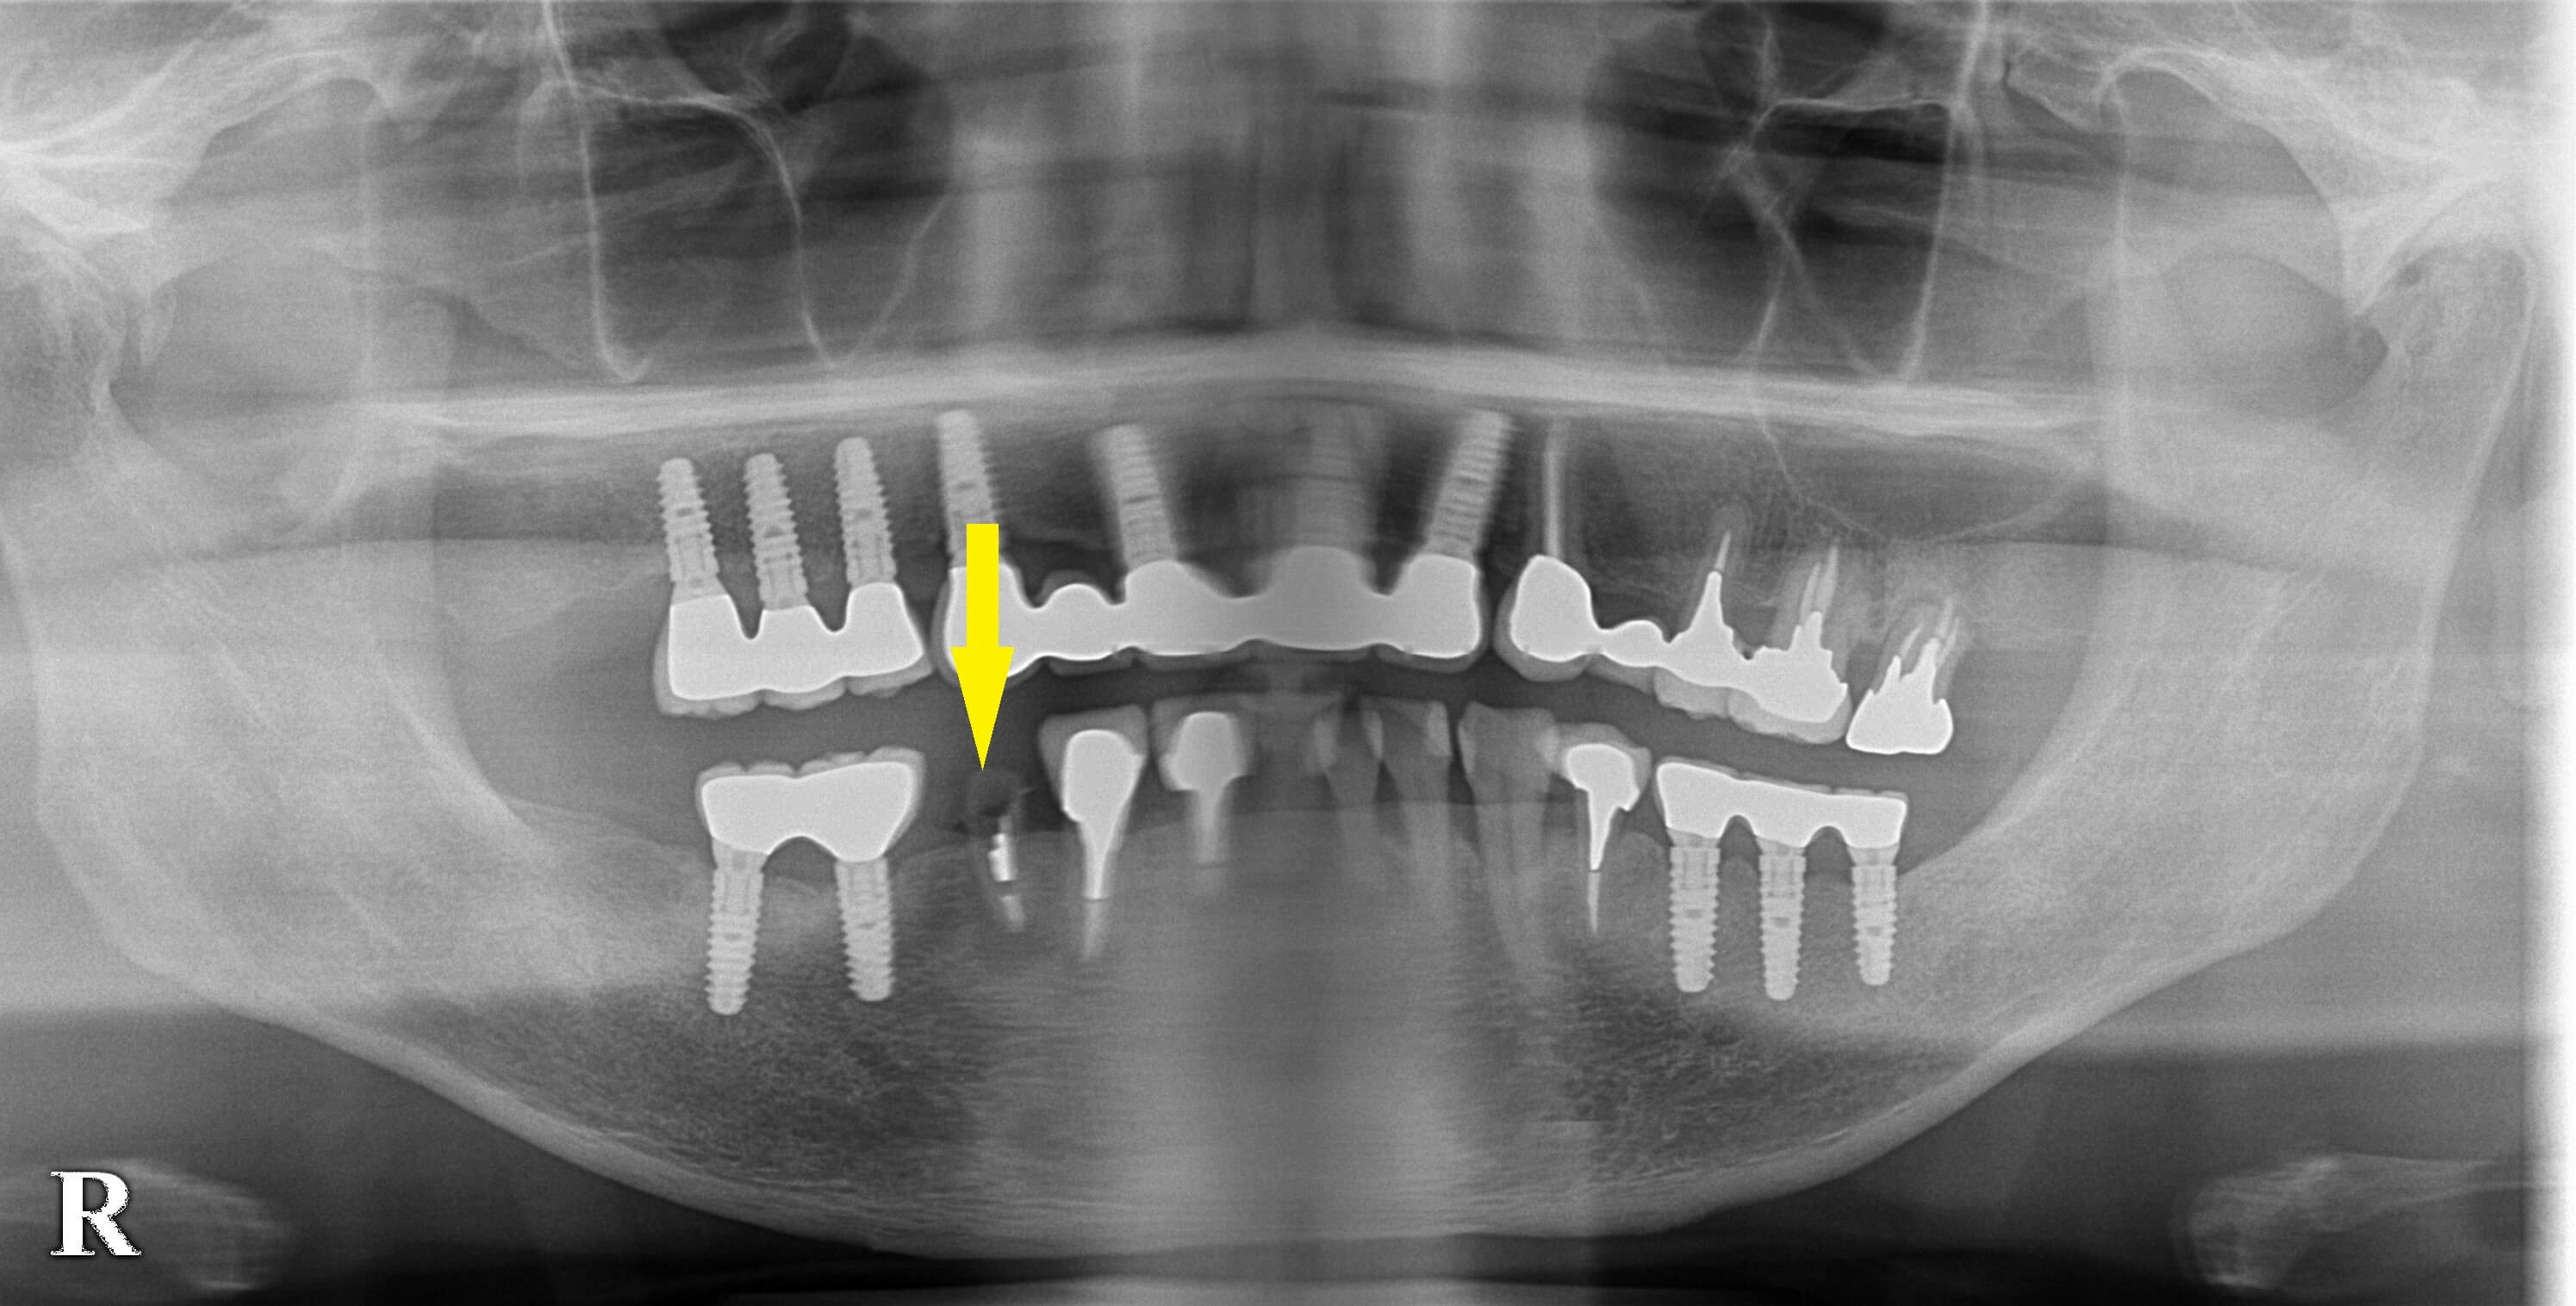

数年前より、順次インプラント治療を行ってきた患者様です。

今回は右下顎第一小臼歯の、かなり古い差し歯が脱離したのですが、歯根の状態が悪く再度差し歯をするのは無理でした。

歯根の先に炎症を起こして、膿がたまっているような状態でしたので、抜歯してインプラント治療を勧めました。

歯根の状態は悪かったのですが、抜歯即時埋入を行って、治療期間を短縮したいと思いましたので、本日抜歯後、インプラント埋入を施行しました。

歯根の周りの炎症を起こした組織を十分に除去して、インプラントを埋入しました。